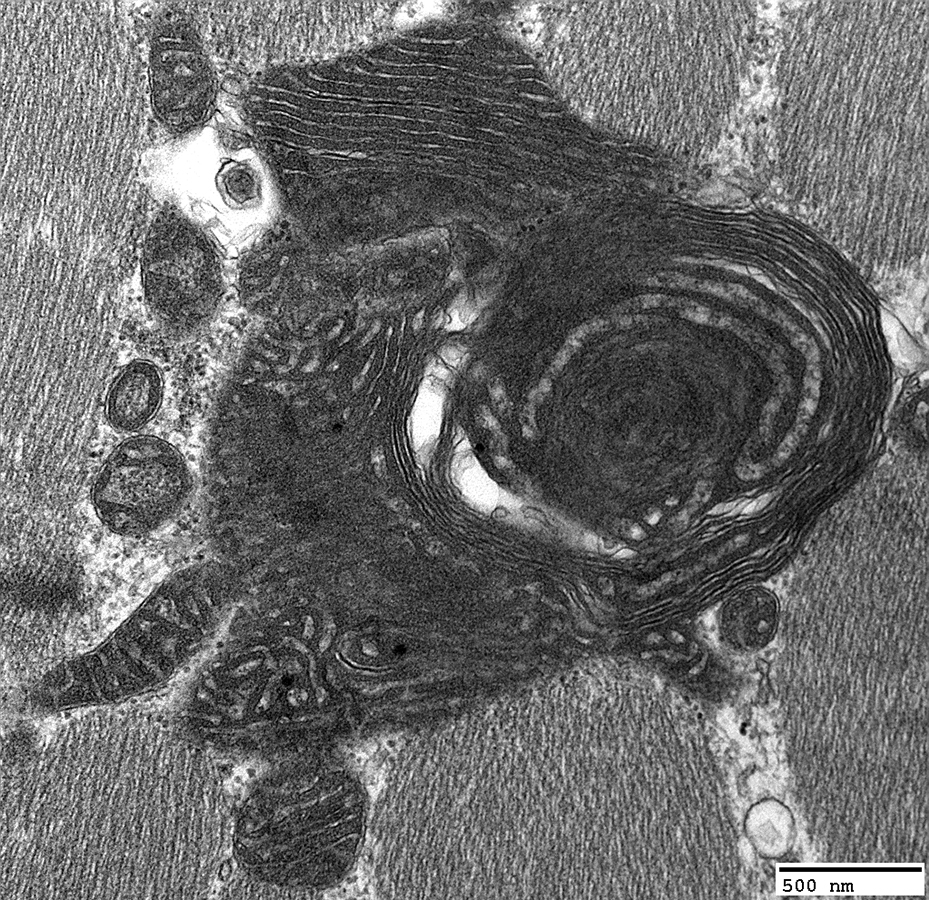

Twinkle: Muscle Ultrastructure

Mitochondrial Proliferation

From: R Schmidt; C Cai

Mitochondria: Subsarcolemmal accumulations

Many mitochondria are abnormal: Large; Long; Dark-stained